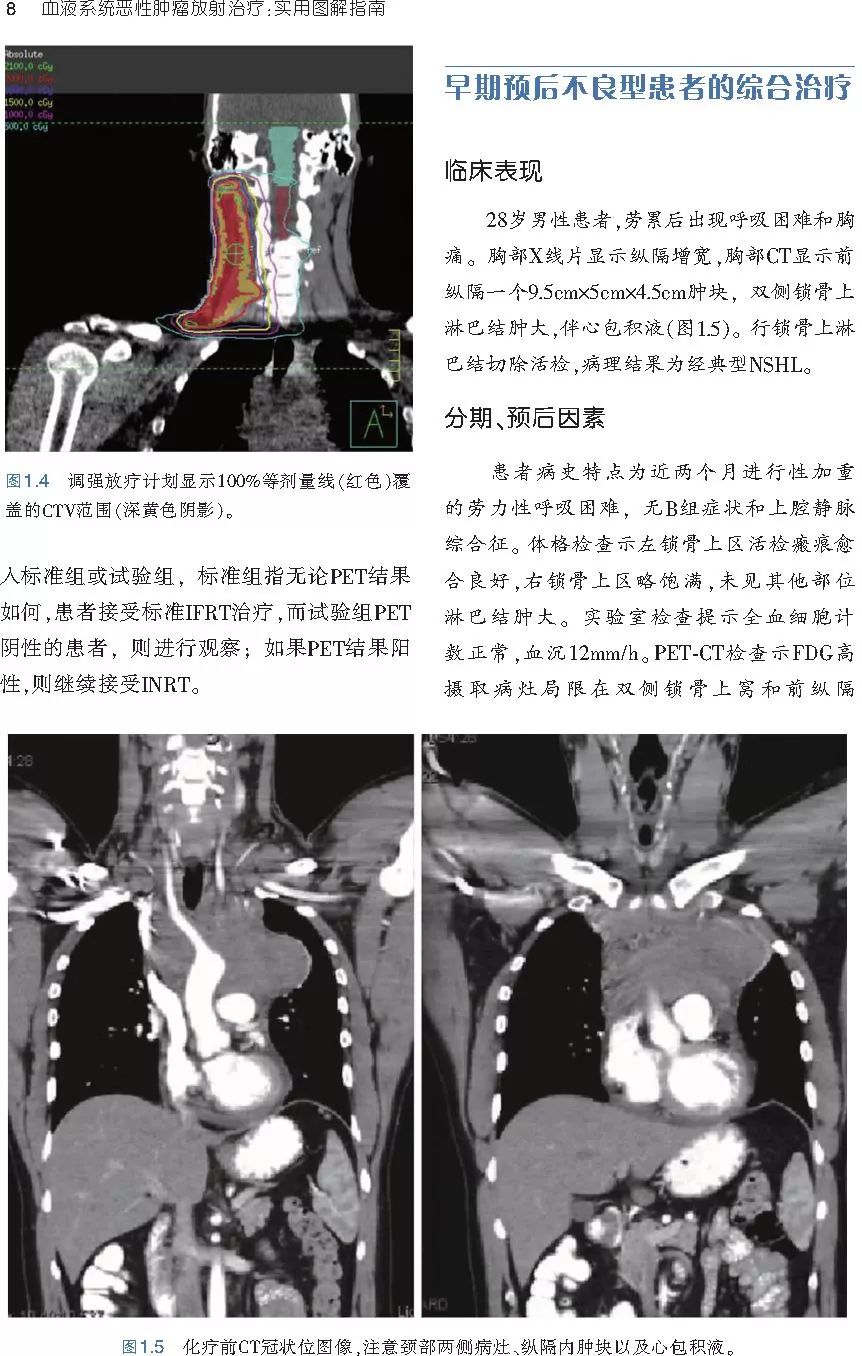

本书旨在帮助临床医生对常见血液系统恶性肿瘤疑难病例进行管理,包括霍奇金淋巴瘤、非霍奇金淋巴瘤和白血病患者,并通过多个病例进行阐述。案例讨论遵循标准格式,包括临床描述,其次是与诊断相关的病理描述和分期,然后详细讨论治疗选择。最后,确定治疗方案,并提供所使用的规划放疗技术/方式的图像。对放射肿瘤医生进行临床决策非常有帮助,针对血液病临床医生也有很好的指导作用。